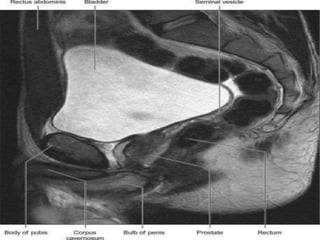

The urinary bladder develops during the 18th week of fetal development. It is located in the pelvic cavity behind the pubic symphysis in males and anterior to the uterus in females. The bladder has a muscular wall and receives its blood supply from branches of the internal iliac artery, including the superior and inferior vesical arteries. Nerve supply comes from pelvic splanchnic nerves via the hypogastric plexus and pudendal nerves. The bladder drains lymph into pelvic lymph nodes and is supported by ligaments attached to surrounding structures in the pelvis. Microscopically, it has a mucosa, submucosa, muscularis and adventitia layers.